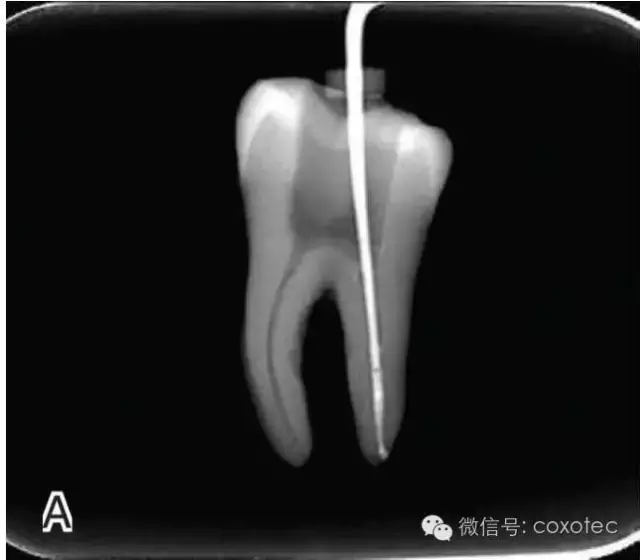

選擇非標(biāo)準(zhǔn)牙膠尖(如0.04、0.06 錐度牙膠尖)作為主尖,型號(hào)一般與根管預(yù)備最大號(hào)的器械型號(hào)一致,能到達(dá)距根尖0.5~1 mm 處,主尖尖段與根管壁緊密接觸。拍試尖X 線片進(jìn)行確認(rèn)(圖3)。

圖3 試尖,A.試主尖 B.拍試尖X片